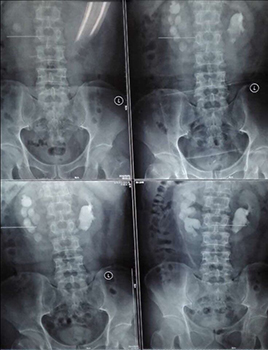

兩位患者均因腰背部疼痛來我院看診,住院后行CT等檢查確診為馬蹄腎合并腎結(jié)石,一例左腎結(jié)石大小約2.5cm,另一例右腎結(jié)石大小約3.0cm。

經(jīng)皮腎鏡取石術(shù)是泌尿外科風(fēng)險最大、技術(shù)要求最高的手術(shù)之一,而馬蹄腎是一種先天性畸形,本該相對獨立的左右兩腎的上端或者下端長在一起,形似“U”形馬蹄,且腎旋轉(zhuǎn)不良,腎盞位于腎前方,輸尿管走形異常,所以馬蹄腎患者更易出現(xiàn)各種合并癥,例如泌尿系統(tǒng)結(jié)石、感染、腎積水、尿路梗阻等。這種腎畸形增加了經(jīng)皮腎鏡取石手術(shù)的定位穿刺和建立操作通道的難度,術(shù)中出血風(fēng)險也更高。如果通道建立不理想,可能找不到結(jié)石,無法完成碎石取石。

馬蹄腎